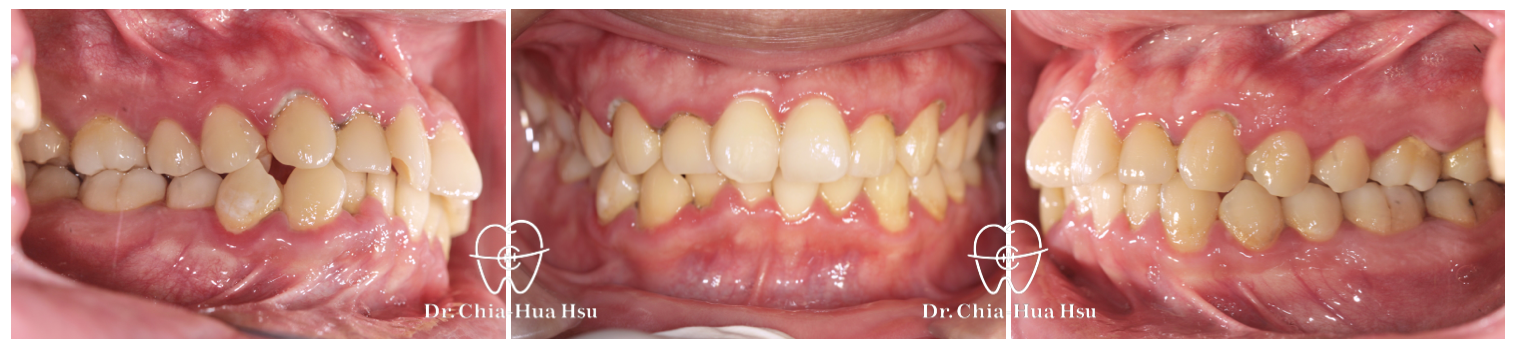

治療前

治療後